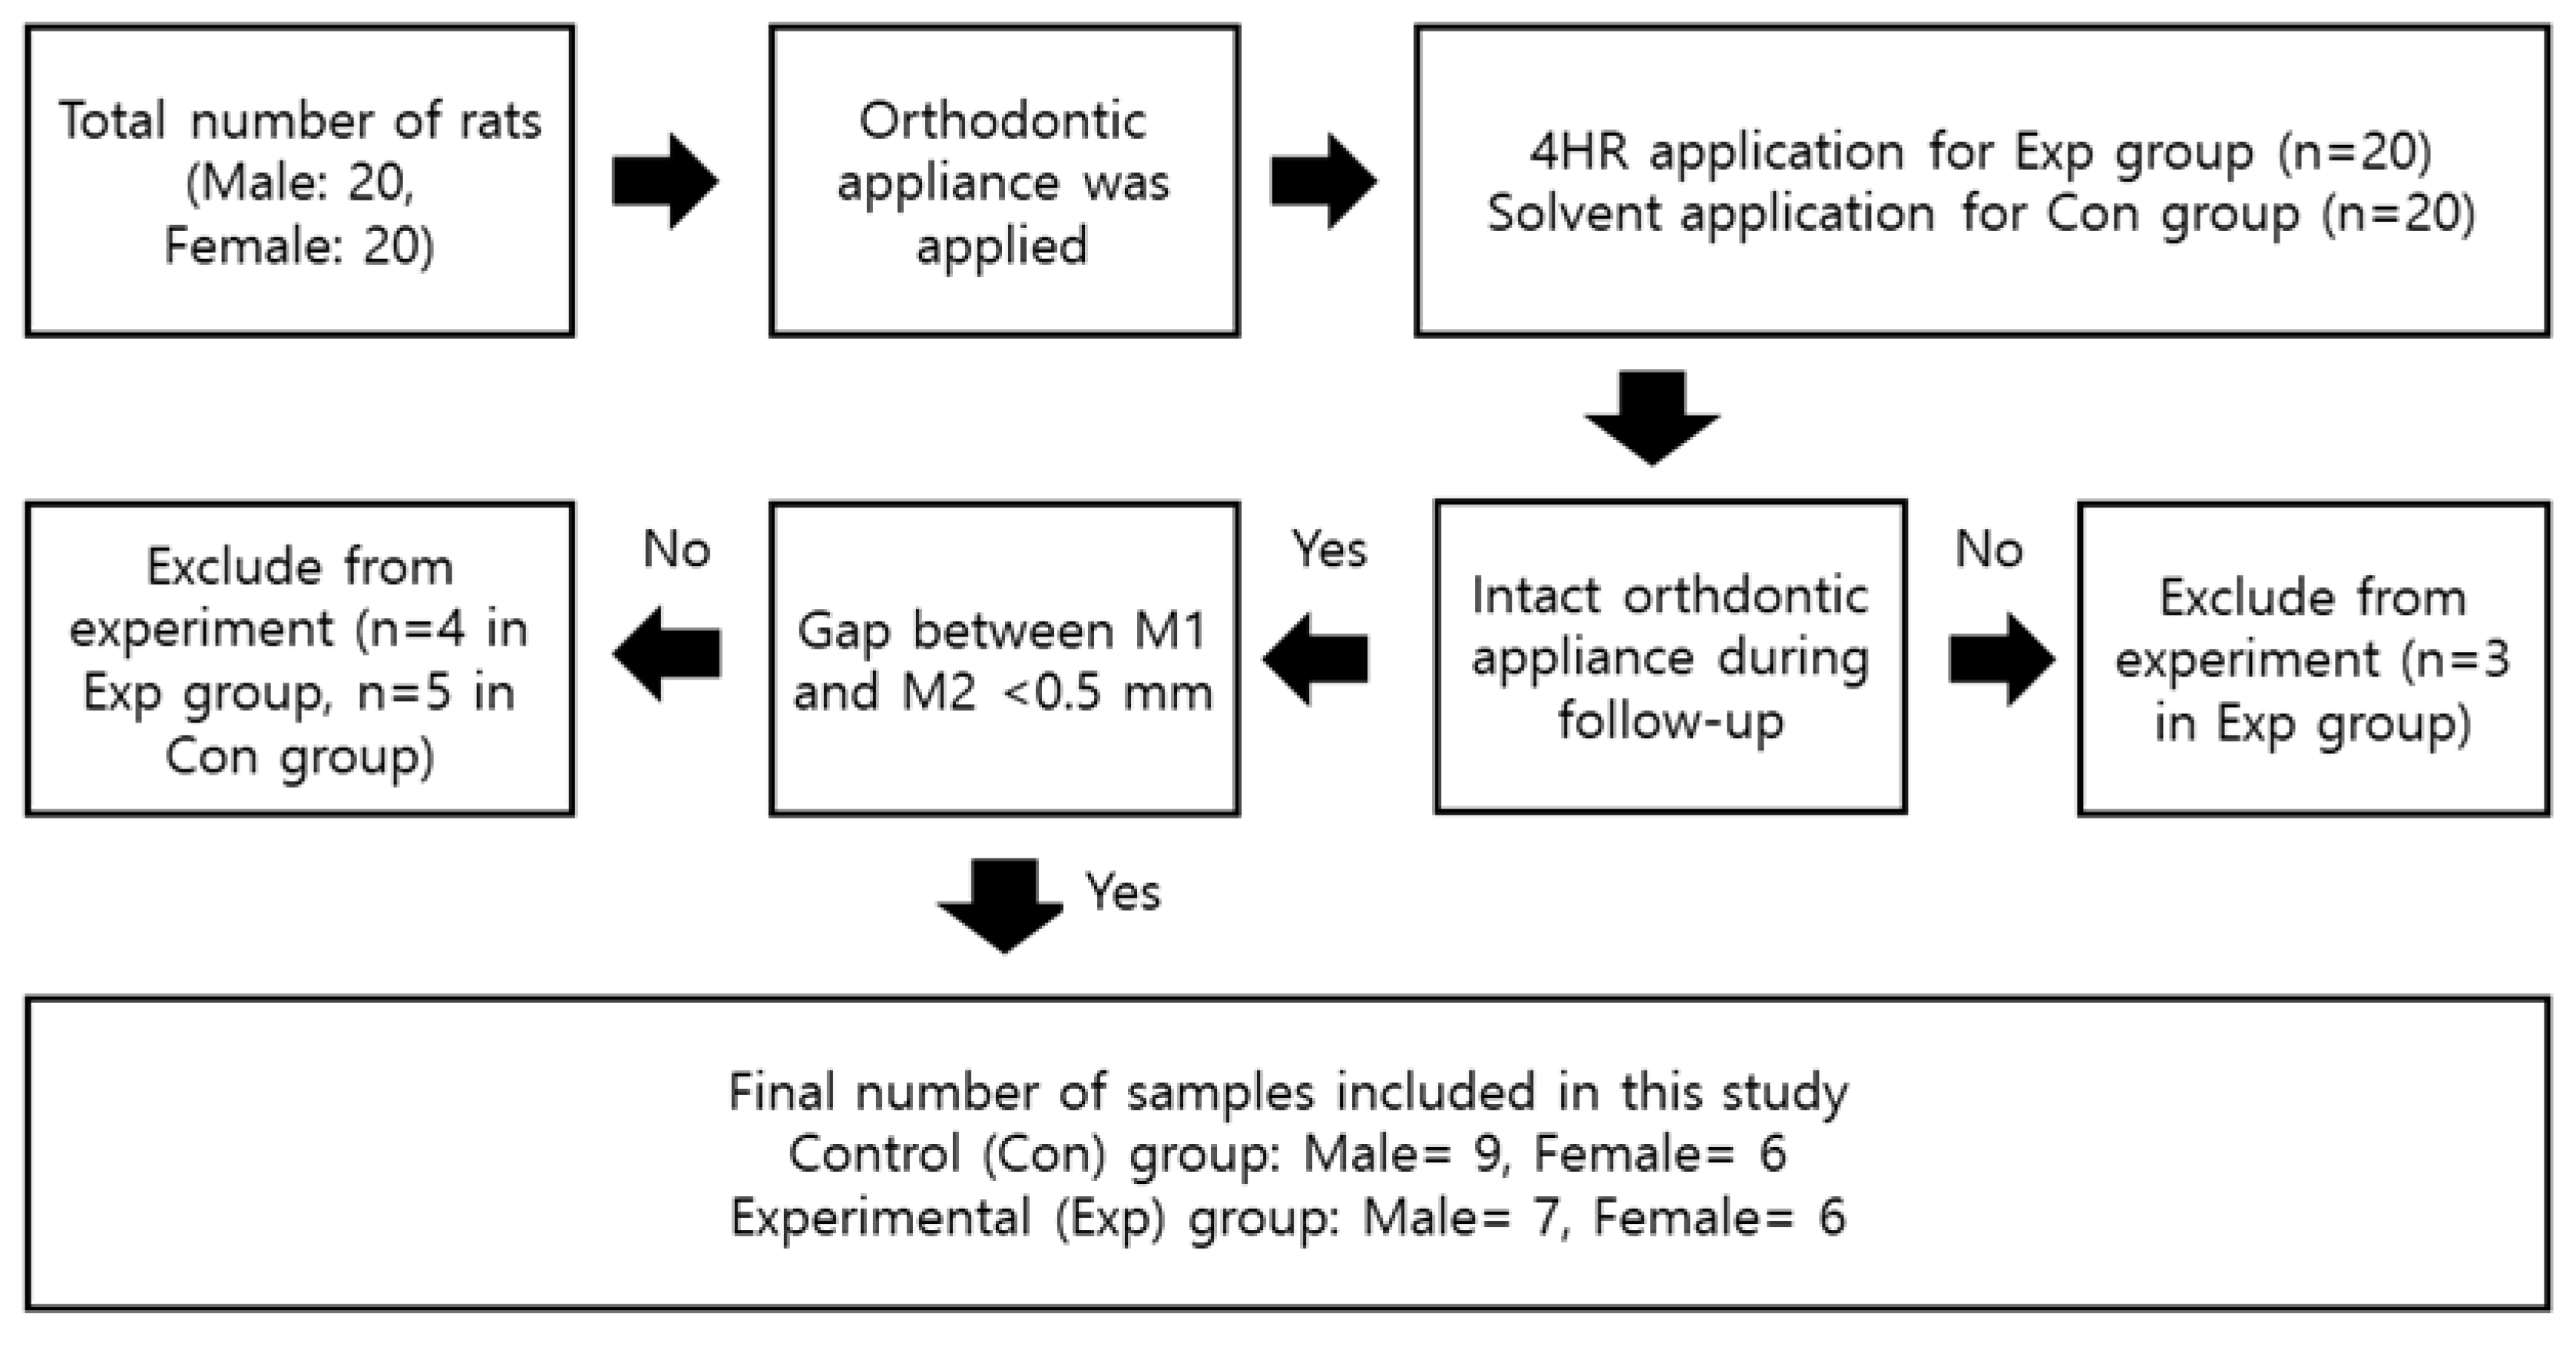

2.1. Animals and Experimental Design

3. Results

3.1. The Application of 4HR Inhibited Root Resorption during OTM